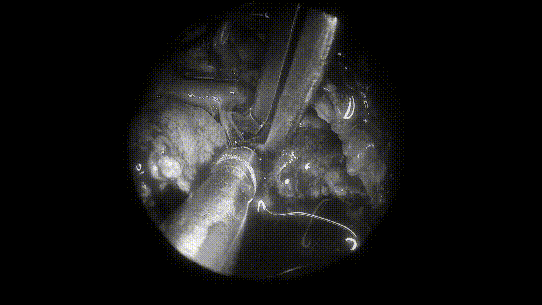

▼INC福教授术中操作步骤图解

术中操作步骤图解

取出部分肿瘤,进行瘤内减压

将肿瘤分离出来——Basilar Artery,基底动脉;Left VA,左侧椎动脉; Right VA,右侧椎动脉;